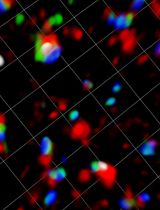

This protocol describes a novel technique to investigate the microcirculation dynamics underlying the pathology in the small intestine of neonatal mice using two-photon laser-scanning microscopy (TPLSM). Recent technological advances in multi-photon microscopy allow intravital analysis of different organs such as the liver, brain and intestine. Despite these advances, live visualization and analysis of the small intestine in neonatal rodents remain technically challenging. We herein provide a detailed description of a novel method to capture high resolution and stable images of the small intestine in neonatal mice as early as postnatal day 0. This imaging technique allows a comprehensive understanding of the development and blood flow dynamics in small intestine microcirculation.

In recent years TPLSM has become increasingly popular in in vivo research. However, intravital imaging of the small intestine in neonatal mice has been challenging due to their small body size and fragility of the intestinal wall. We have developed a novel application of TPLSM to visualize and study the small intestine of neonatal mice in vivo.

Our method allows for direct microvascular blood flow analysis. Stappenbeck TS et al. (2002) reported a method to analyze intestinal microcirculation indirectly from intestinal tissue samples harvested immediately after injecting fluorescein isothiocyanate-labeled dextran into the heart (Yu et al., 2009; Watkins and Besner, 2013; Yazji et al., 2013). However, thisand other similar methods for intravital imaging of the adult mouse intestine are not functional in blood flow dynamics. Our method allows for blood flow dynamics analysis, and facilitates investigation of intestinal villi development and establishment of the capillary network complexity (Stappenbeck et al., 2002). This protocol will allow the investigation of pathological processes associated with intestinal blood flow dynamics in vivo, thus promoting translational research.

The TPLSM imaging method described here can be easily applied to investigate different physiological processes in the neonatal intestine in multiple mouse models. For example, we are using this method to study blood flow dynamics and inflammatory responses in necrotizing enterocolitis (NEC), intestinal epithelium and micro-vasculature development in short bowel syndrome (SBS), inflammatory and immunological status in inflammatory bowel disease (IBD), and ischemia-reperfusion injury in midgut volvulus. Previous studies investigated neonatal intestinal microcirculation in experimental NEC ex vivo, however, these studies did not consider the effects of blood flow dynamics in capillary-vessels in the villi. Our new method allowed us to measure neonatal intestinal microcirculation from movies of live blood flow and to derive blood flow velocity, vessel diameter and inflammation, and assess irrigation of the serosal and mucosal layers. Moreover, this technique is being used to visualize and quantify live blood flow dynamics during reperfusion and ischemia in experimental midgut volvulus, which will be useful to identify the primary intestinal tissues affected.